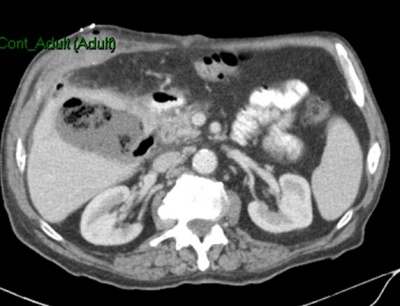

במעבדה אין מאפיינים מיוחדים. האבחנה מתבצעת על-ידי בדיקת אולטרה-סאונד, שהיא בדיקת בחירה לאבחון אבנים בכיס המרה בשל היותה בדיקה בלתי פולשנית בעלת אמינות גבוהה. בבדיקת האולטרה-סאונד יודגמו אבנים בכיס המרה ככתמים בהירים בתוך הכיס, הנעים בשינוי תנוחה. מאחוריהם ניתן לראות את הצל האקוסטי (Acoustic shadow) (תצלום 19.8). שני ממצאים אלה הם הסימנים המובהקים לאבני מרה. בבדיקה זו אפשר לבדוק את קוטר דרכי המרה החוץ-כבדיות. רק 20% מהאבנים בדרכי המרה מודגמות בשיטה זו. כמו-כן אפשר למדוד את קוטר כיס המרה ואורכו. בדיקות אלה אמינות ב- 94%-90%. לעיתים האבנים אינן נראות בברור ב- US אבל נראות ב- אולטרה-סאונד אנדוסקופי (EUS) או מאובחנות ב- CT (תצלום 20.8).